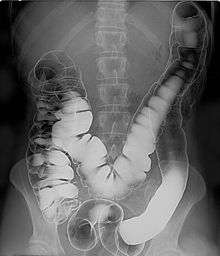

Air

Barium sulfate is mainly used in the imaging of the digestive system. The substance exists as a water-insoluble white powder that is made into a slurry with water and administered directly into the gastrointestinal tract.

- Barium enema (large bowel investigation) and DCBE (double contrast barium enema)

Barium sulfate, an insoluble white powder is typically used for enhancing contrast in the GI tract. Depending on how it is to be administered the compound is mixed with water, thickeners, de-clumping agents, and flavourings to make the contrast agent. As the barium sulfate doesn't dissolve, this type of contrast agent is an opaque white mixture. It is only used in the digestive tract; it is usually swallowed or administered as an enema. After the examination, it leaves the body with the feces.